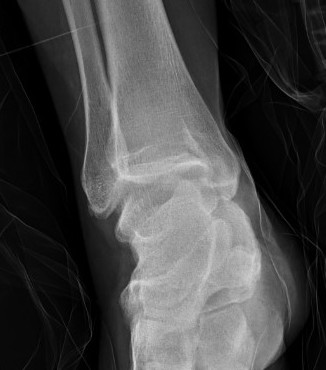

Xray

Syndesmotic injury with high grade deltoid injury

Ankle dislocation with soft tissue injury to Deltoid and syndesmsosis